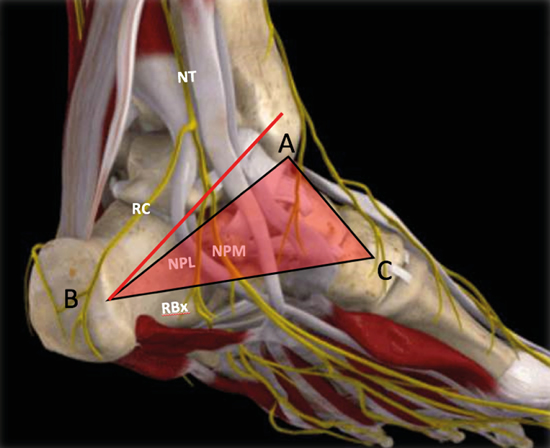

Figura 3. Túnel tibiotalocalcáneo. El nervio tibial (NT) se divide en la rama calcánea (RC), el nervio plantar medial (NPM) y el nervio plantar lateral (NPL) del que se escinde la rama de Baxter (RBx). Las estructuras musculotendinosas tibial posterior (TP), flexor largo del primer dedo (FLD) y flexor largo de los dedos (FCD) acompañan al nervio tibial en su recorrido por la cara medial del tobillo y el pie. Imagen modificada de la App Ankle & Foot Pro III.

Figura 13. Línea de Dellon-Mackinnon (A-B) y triángulo de Heimkes (A-B-C). Se observan el nervio tibial (NT) y las ramas calcánea (RC), el nervio plantar lateral (NPL), el nervio plantar medial (NPM) y la rama de Baxter (RBx). Imagen modificada de la App Ankle & Foot Pro III.